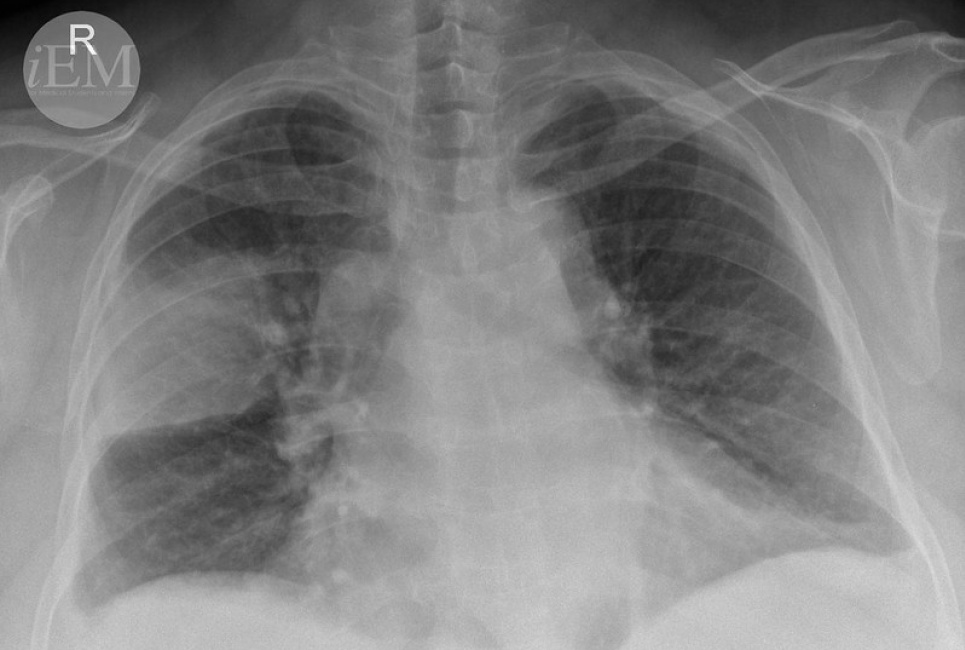

Как можно облегчить течение пневмонии